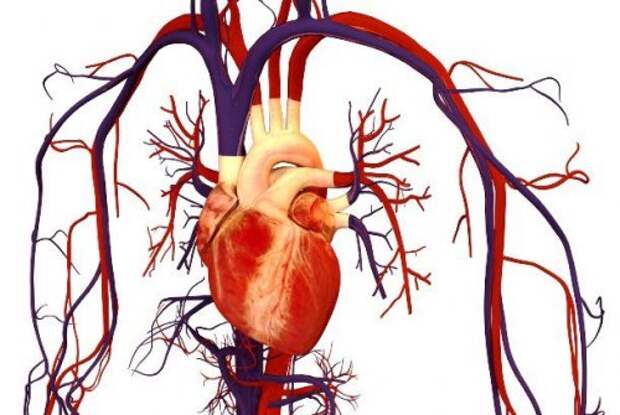

22. Кровообращение

Фото: Bryan Brandenburg

Одним из самых важных открытий в медицине стало открытие системы кровообращения, о чем в 1628 году объявил английский врач Вильям Харви (William Harvey).

Он стал первым человеком, описавшим всю систему циркуляции и свойства крови, которую сердце качает по всему нашему телу от мозга до кончиков пальцев.